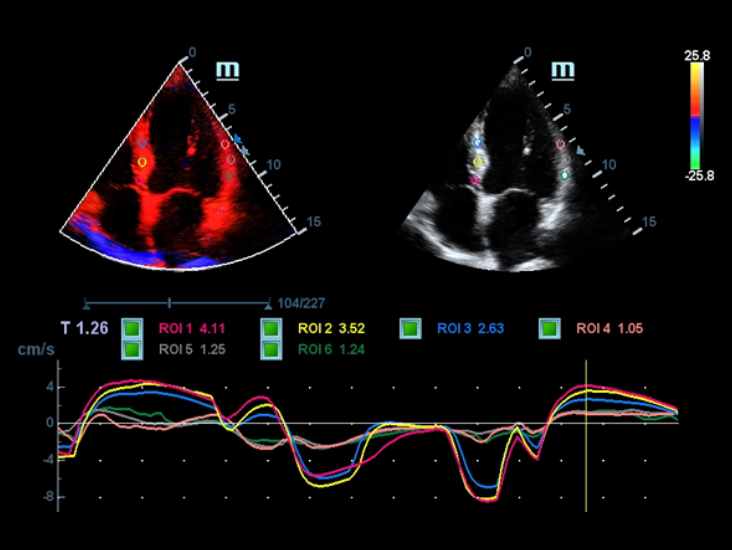

Ak?ll? Takip

Ak?ll? Takip, yaln?zca tek dokunu?la ?al??arak, vaskÞler g?rÞntÞleme i?in h?zl? ve ak?ll? optimizasyon sa?lar. Otomatik takiple, Renk, GÞ? ve PW spektrumunu optimize edebilir ve zaman alan ad?mlar? azaltabilir. Bu nedenle, vaskÞler muayene i? ak??? optimum g?rÞnÞmle basitle?tirilir.